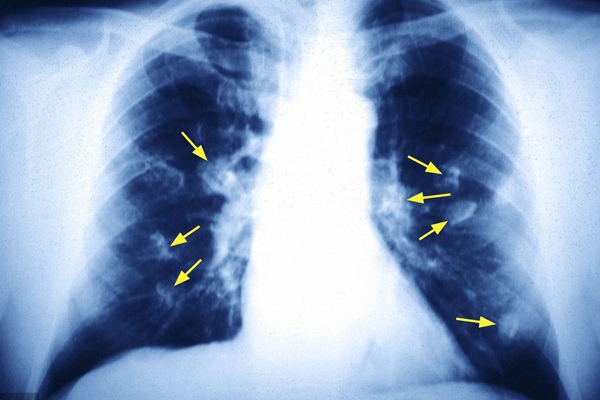

从光滑程度看,良性的结节外形是比较光滑的,并且边界清晰;恶性的结节表面粗糙,边界不清晰。从形状看,良性的肺结节通常是圆形或是椭圆形的;而恶性的结节很少有这两种形状,大多是葫芦状的。从长大的速度来看,良性的结节几个月或是几年可能变化都不是很大;恶性结节很可能会随着时间的变化而慢慢长大。从软硬程度来看,如果是质地较硬的结节通常就是良性的;而恶性结节不会完全钙化的,质地不是很硬。从外侵的迹象来看,良性的结节通常不会有外侵的情况发生,不影响周围的器官组织;恶性结节很大可能会入侵到周围的组织,影响到其它的组织。